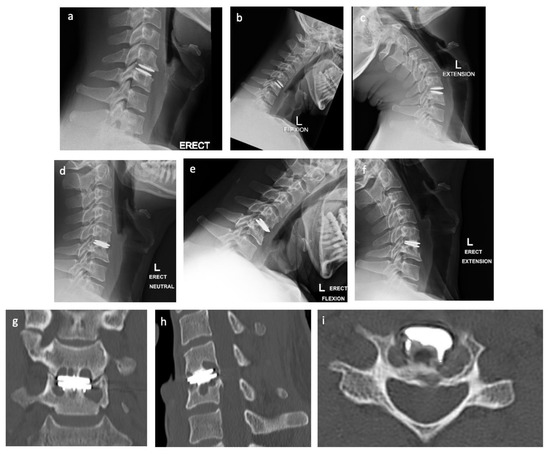

2.1. Case Presentation

2.2. Preoperative Planning

2.3. Operative Technique

3. Results